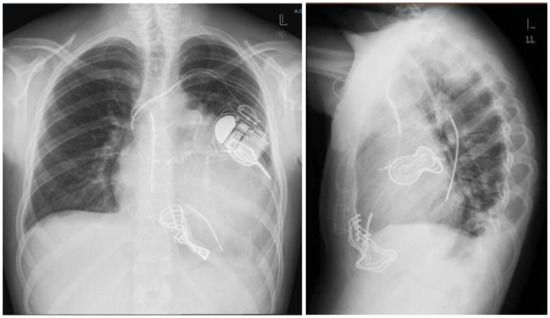

An epicardial defibrillation patch (Medtronic, Inc., ST Anthony, MN, USA) was placed on the left ventricular lateral wall, but again DFT testing was ineffective using the right ventricular (RV) coil to lateral patch as shock pathway. Another epicardial defibrillation patch was then placed on the inferior wall (Figure 2 left panel). In this case, DFT testing was effective with a defibrillation pathway between the two patches and the can. The subcutaneous multi-coli arrays were removed.

Figure 2.

Left panel. AP chest X-ray showing dual-chamber ICD connected to two epicardial patches (lateral and inferior). The defibrillation pathway is between the two patches and the can (red arrows). Figure 2 right panel. CT scan shows strong adhesion of the patches with the underlying myocardium.

In September 2012, the left lateral epicardial patch showed high impedance (>200 ohm), indicating it was damaged. The inferior patch–can shock pathway was then programmed.

Several options were considered. The first one was surgical removal and replacement of the broken epicardial patches, but this was considered too dangerous due to possible strong adhesions of the patches with the underlying myocardium, with consequent risk of myocardial rupture (Figure 2 right panel).